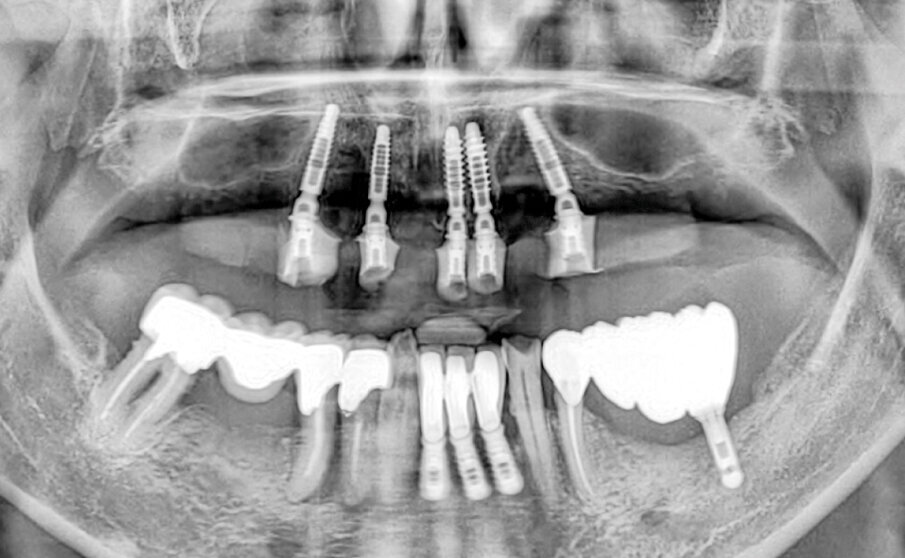

Con il software della CBCT viene progettato il posizionamento di cinque impianti nelle posizioni 15, 13, 21, 22, 25 inclinando i due impianti distali lungo la parete dei seni mascellari (Fig. 2). Questo studio iniziale software-assistito ci sarà di grande aiuto anche se non tradotto in una dima chirurgica per implantologia guidata.

Fig. 2 - Progettazione 3D.